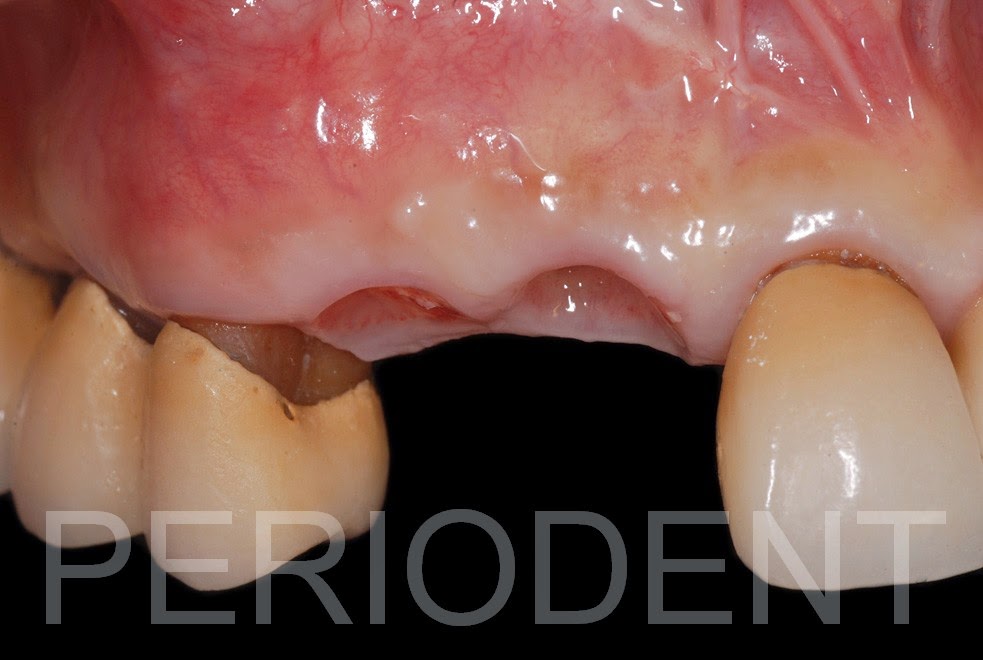

植牙手術完拆線及癒合後